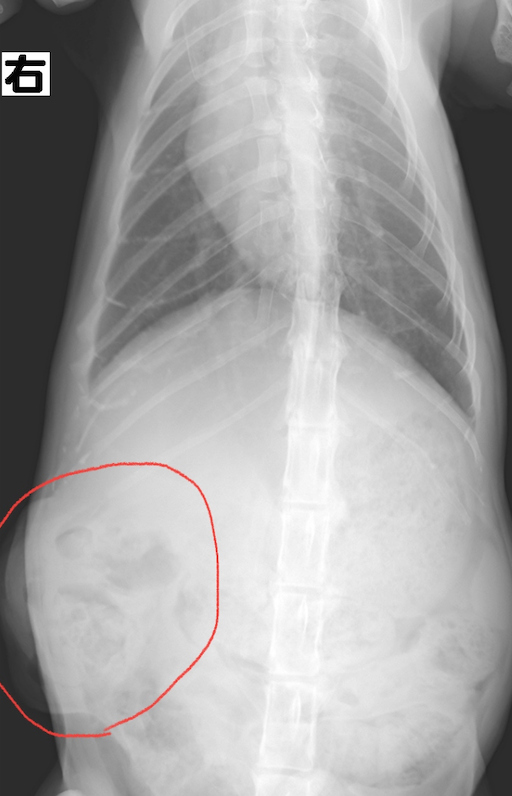

レントゲンを撮ってみると、、、

お臍の所と右側のお腹の所から脂肪組織や消化管の一部が飛び出てしまってます。

触診、レントゲンの結果から「腹壁ヘルニア」と診断しました。